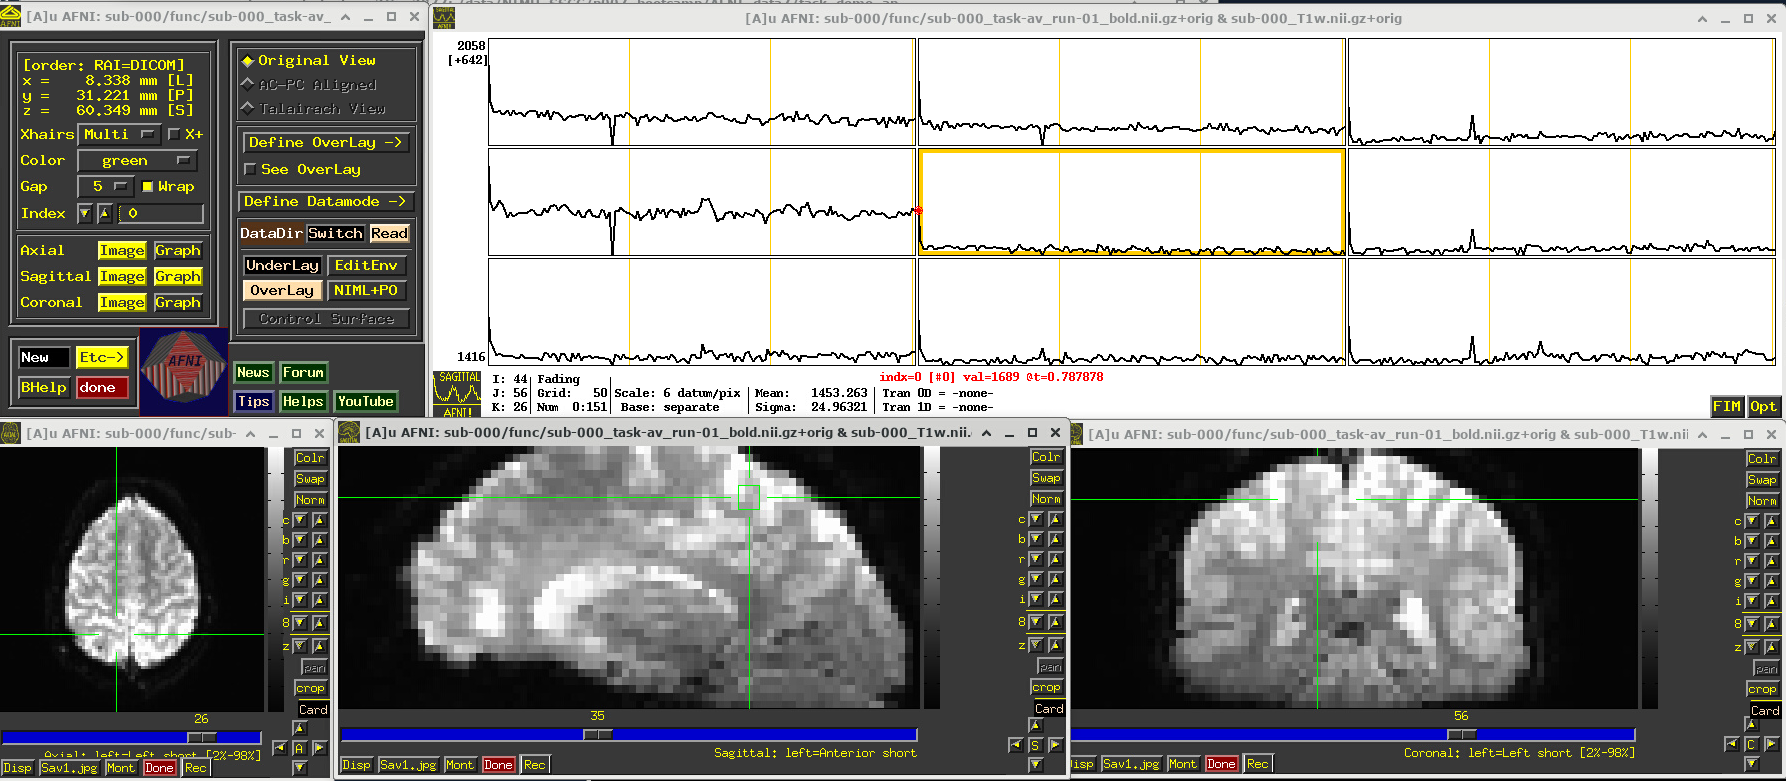

# Display a screenshot of the AFNI GUI with the first EPI run loaded, seen at coordinate origin

IPython.display.Image(filename='example_snapshots/img_01_afnigui_epi_r01_000.png')

../_images/230cc87850086d0cc51017fcc155a583ecb39e569916ab90b26550ade057de65.png

In the Image panels, you see a fuzzy-looking brain, with some cortical patterns visible, but tissue boundaries and regions probably aren’t as obvious as in the anatomical dataset view, above.

In the Graph panel, you are seeing a montage of time series from a (default) 3x3 grid of voxels in the given sagittal slice. In this subcortical region, the time series have a lot of fluctuations and don’t have a recognizable pattern.